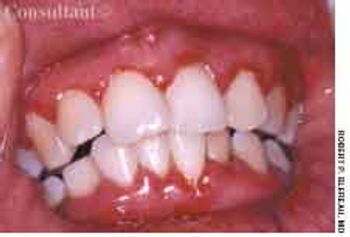

A 25-year-old primipara had her first prenatal visit at 12 weeks' gestation. She said that her gums had recently become irritated and bled easily.